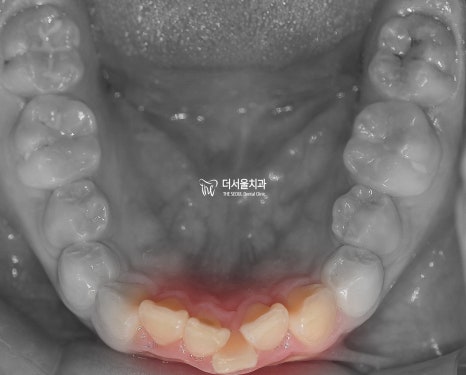

구강 사진을 보면

윗니가 뻐드러져 있는 걸 볼 수 있으며

아랫니는 치열이 고르지 못한 것을 알 수 있었습니다.

정면과 측면에서 봤을 때

하악 전치부가 거의 보이지 않을 정도로

심한 과개 교합을 양상을 나타내고 있었습니다.

전체적으로

문제점을 종합해 보면

2급 부정교합과 과개 교합을 나타내고 있었습니다.